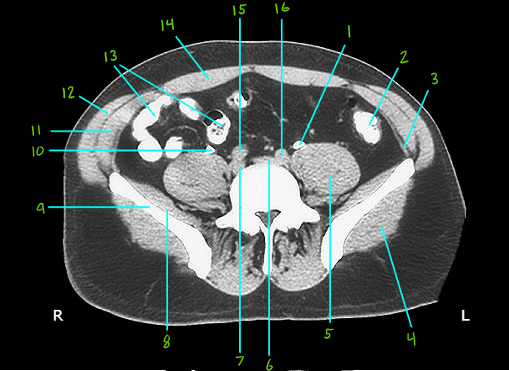

1

Q

What is #1

A

Left ureter

2

What is #2

Sigmoid colon

3

What is #3

Transverse abdominis muscle

4

What is #4

Gluteus maximus muscle

5

What is #5

Posas major muscle

6

What is #6 & 7

R and L common iliac veins

7

What is #8

Iliacus muscle

8

What is #9

Ala of the illium

9

What is #10

Right ureter

10

What is #11

Internal oblique muscle

11

What is #12

External oblique muscle

12

What is #13

Ileum

13

What is #14

Rectus abdomins ,uscle

14

What is # 15 & 16

R and L commin iliac arteries